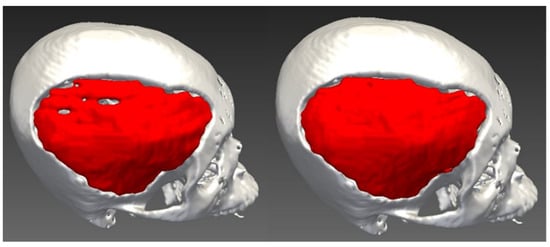

2.1. Design of Cranial Implants Using 3-Matic Software

2.2. Design of Cranial Implants Using MITK Software